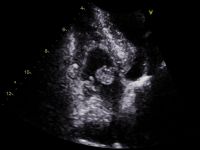

If you have been asked to attend for a contrast echocardiogram, you may be wondering exactly what one is,

Before any operation requiring general anaesthetic, an anaesthetist may request a preoperative echocardiogram. They will mainly be interested in

A myxoma is a non-cancerous tumour in the heart. They are more common in women, and are also most frequently